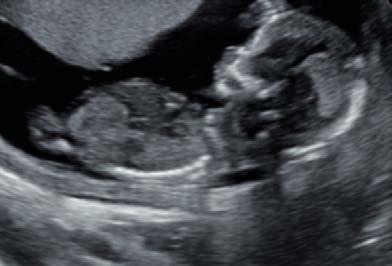

Echo’s spelen een belangrijke rol tijdens de zwangerschap.Ze bieden een uniek kijkje op de ontwikkeling van het kindje in de buik. Er zijn echter twee verschillende soorten echo’s: medische echo’s en pretecho’s. Het is belangrijk om het onderscheid tussen deze twee te kennen, vooral omdat pretecho’s steeds populairder worden.

Medische echo’s: gericht op gezondheid en diagnostiek Medische echo’s worden uitgevoerd door gekwalificeerde echoscopisten en vallen onder de zorg die een verloskundige of gynaecoloog aanbiedt. Deze echo’s hebben een medisch doel en worden ingezet om de gezondheid van moeder en kind te controleren. De Beroepsvereniging Echoscopisten Nederland (BEN) waarborgt de kwaliteit en professionaliteit van deze echo’s.

De meest voorkomende medische echo’s zijn:

• Termijnecho (9-13 weken): Bepaalt de uitgerekende datum en bevestigt of het om een eenling- of meerlingzwangerschap gaat.

• 13-weken echo (1e trimester structureel echoscopisch onderzoek): Screeningsonderzoek naar structurele afwijkingen bij de baby.

• 20-weken echo (2e trimester structureel echoscopisch onderzoek): Controleert op aangeboren afwijkingen en de ontwikkeling van de organen.

• Groeiecho: Wordt op medische indicatie uitgevoerd om de groei van de baby en de hoeveelheid vruchtwater te beoordelen.

• Liggingsecho (vanaf 36 weken): Controleert of de baby in de juiste positie ligt voor de bevalling.

Pretecho’s: een persoonlijke herinnering

Pretecho’s zijn niet-medische echo’s die je op eigen verzoek kunt laten doen wanneer jij dat wilt. Ze hebben als doel om ouders een extra moment te geven om hun baby te bewonderen, vaak in 2D, 3D of 4D beeld. Deze echo’s kunnen op elk moment in de zwangerschap worden uitgevoerd, maar bieden geen medische informatie over de baby.

Veel ouders kiezen voor een pretecho om achter het geslacht van het kindje te komen of om samen met eventueel aanstaande broertjes/zusjes en opa’s/oma’s de baby in een ontspannen sfeer te bewonderen en herinneringen te maken. De 3D/4D echo is vooral geliefd, omdat deze een gedetailleerd beeld van het gezichtje van de baby geeft. Soms zie je de baby zelfs lachen of gapen! Dit kan helpen om een nog sterkere band met je baby te voelen. Hoewel pretecho’s geen medische functie hebben, kunnen ze bijdragen aan een bijzondere ervaring tijdens de zwangerschap.